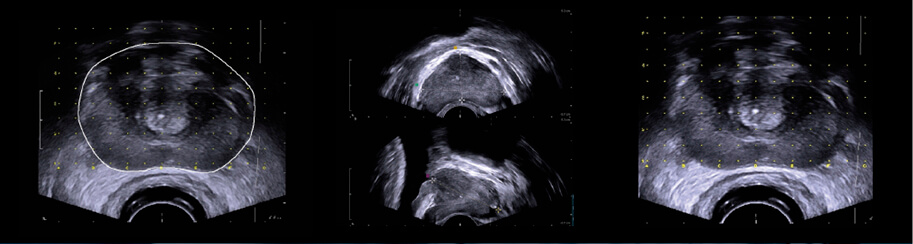

Este transdutor biplanar oferece um modo de aquisição diferenciado onde é possível adquirir simultaneamente duas imagens em tempo real – cortes longitudinais e transversais.

Com a imagem biplanar é possível verificar a posição e, principalmente, a profundidade da agulha no momento da biópsia da próstata.